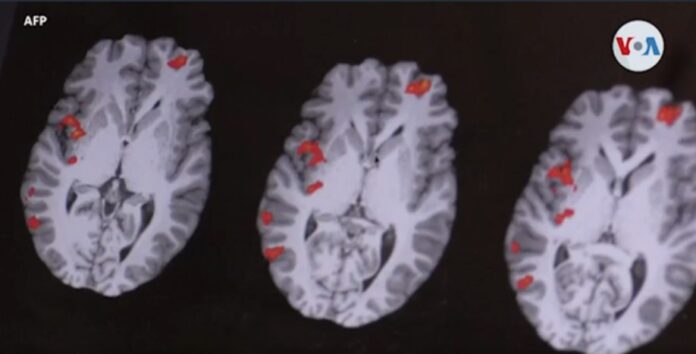

Washington, DC. (VOA) – Entender los mecanismos del cerebro detrás del desorden afectivo estacional fue uno de los objetivos de un equipo de investigadores que, de acuerdo a su análisis, ha demostrado que la duración de la luz del día afecta los receptores encargados de regular nuestro estado de ánimo.